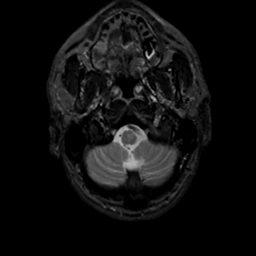

MR Study #7, March 24, 1991 -- Slice #4